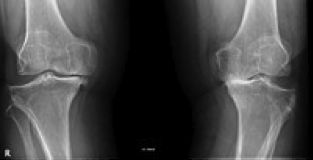

ARTROSIS DE RODILLA (GONARTROSIS)

La Artrosis es una enfermedad degenerativa de las articulaciones. Consiste en la pérdida del cartílago articular, la formación de osteofitos y la deformación de la articulación afectada. Existen factores desencadenantes, como un traumatismo importante, y factores que aceleran la progresión de la artrosis, como la inestabilidad o la sobrecarga mecánica de la articulación afectada. También existe una predisposición genética a padecer la enfermedad. Las articulaciones más afectadas son la rodilla, la cadera, las articulaciones de las manos y la columna vertebral cervical y lumbar.